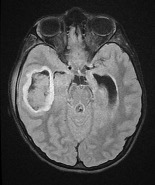

Diagnostic testing. Findings from the laboratory studies revealed an elevated white blood cell count of 33.09 c/mL, an elevated erythrocyte sedimentation rate of 122 mm/hr, and an elevated procalcitonin level of 9.61 ng/mL. Thus, the patient was started on cefepime and levetiracetam. Imaging studies demonstrated mastoiditis, a large right temporal collection of fluid concerning for early cerebritis, and ventriculitis with abscess formation and local mass effect (Figures 1-4).

Figure 2. Axial T2 flair magnetic resonance imaging demonstrated a right temporal lobe abscess.